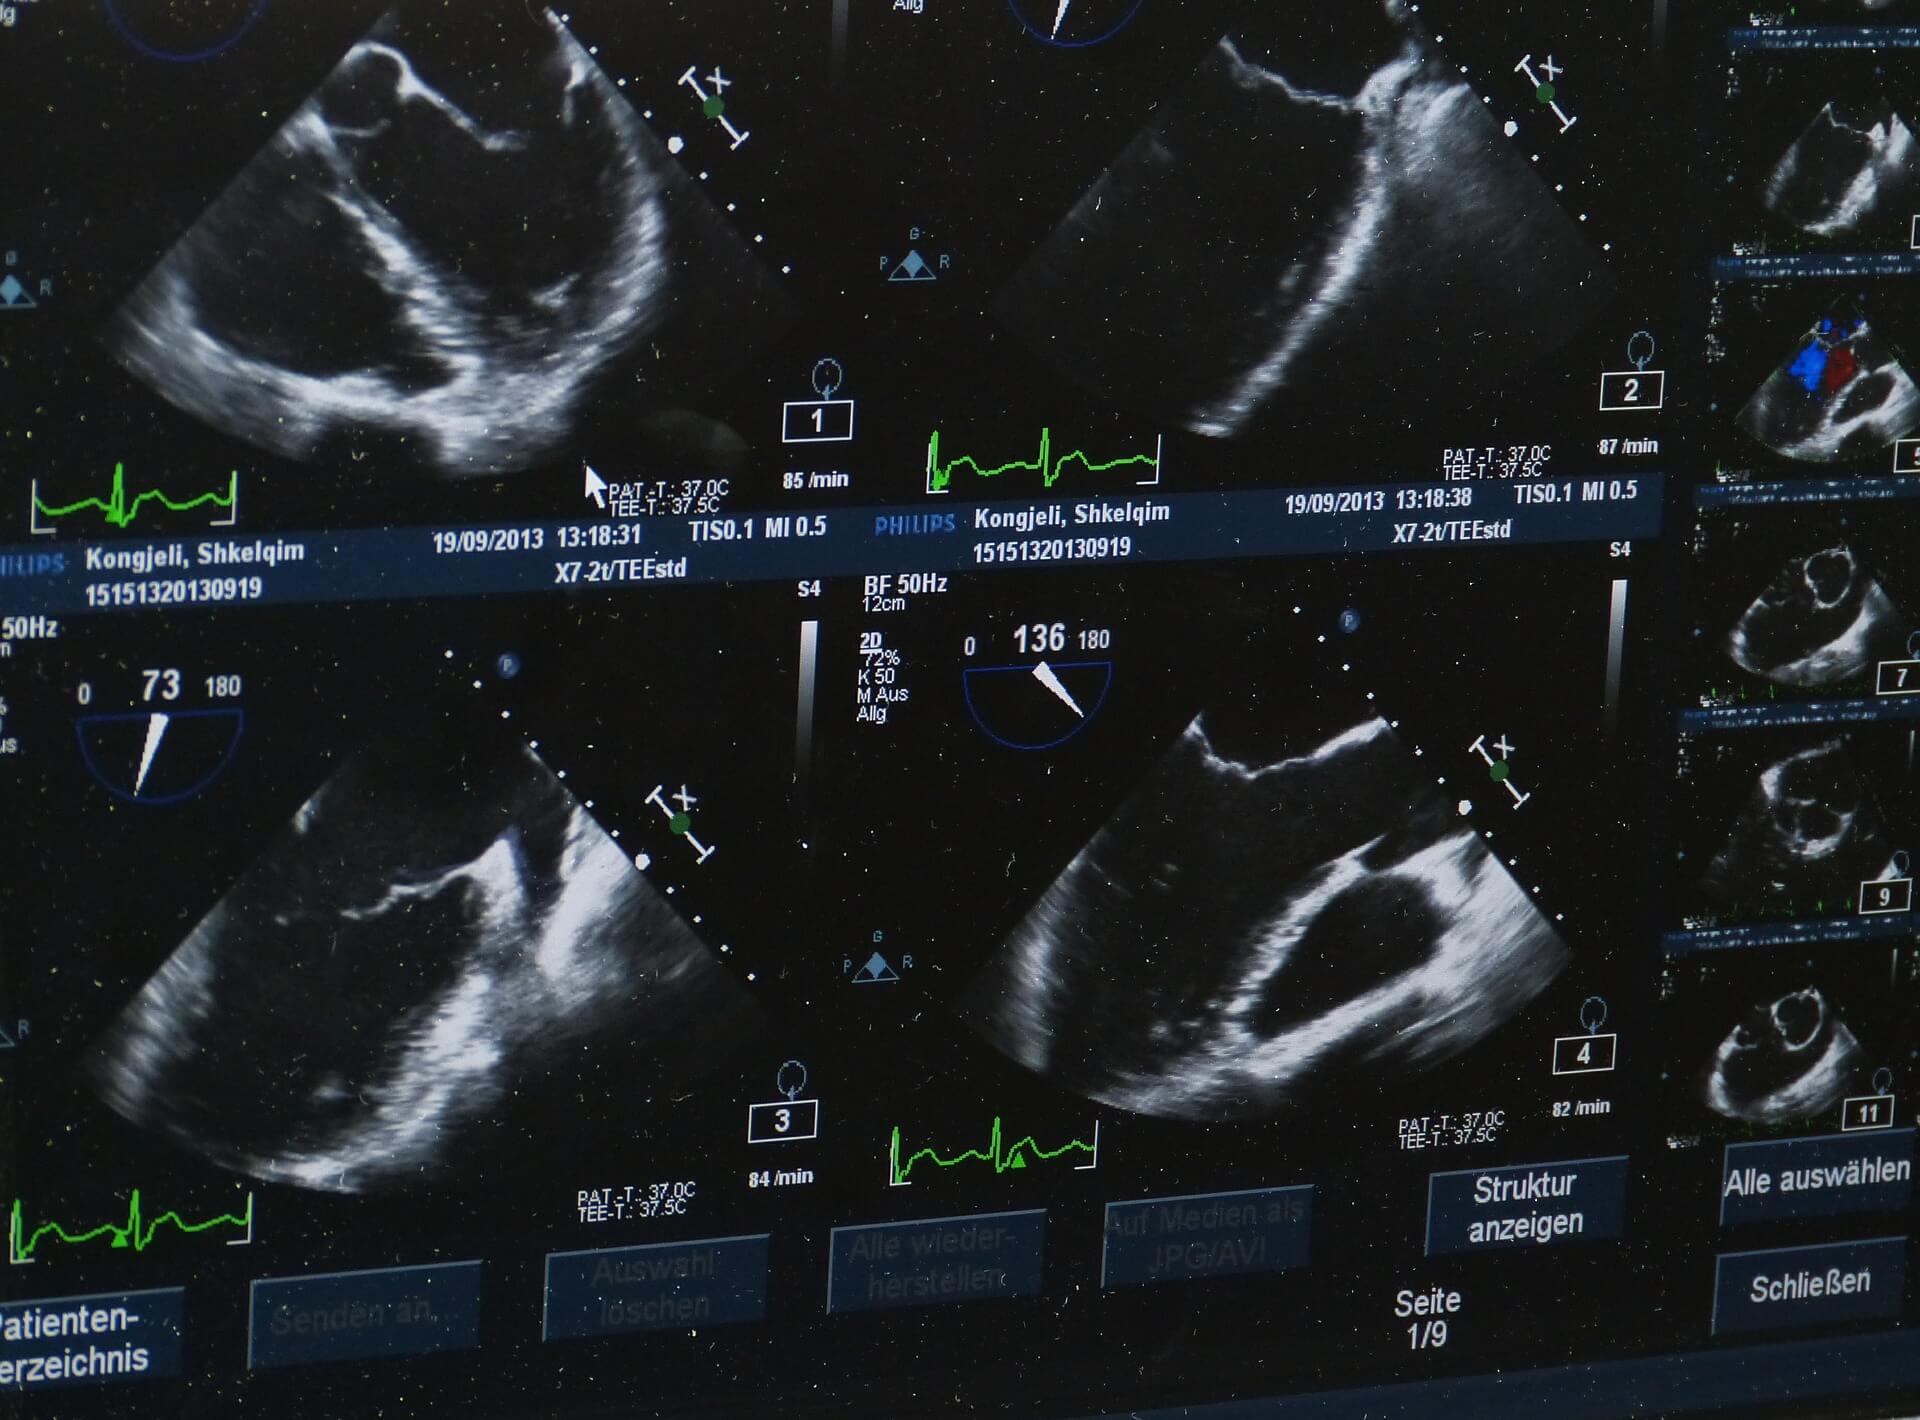

W badaniu ultradźwiękowym przetwornik zarówno wysyła fale dźwiękowe, jak i rejestruje fale echa. Gdy przetwornik jest dociskany do skóry, wysyła do ciała niewielkie impulsy niesłyszalnych fal dźwiękowych o wysokiej częstotliwości. Gdy fale dźwiękowe odbijają się od narządów wewnętrznych, płynów i tkanek, czuły odbiornik w przetworniku rejestruje niewielkie zmiany wysokości i kierunku dźwięku. Te fale charakterystyczne są natychmiast mierzone i wyświetlane przez komputer, który z kolei tworzy obraz w czasie rzeczywistym na monitorze. Jedna lub więcej klatek ruchomych obrazów jest zazwyczaj rejestrowanych jako obrazy nieruchome. Można również zapisać krótkie pętle wideo obrazów.

Ultrasonografia dopplerowska, specjalna technika ultradźwiękowa, mierzy kierunek i prędkość komórek krwi poruszających się przez naczynia. Ruch komórek krwi powoduje zmianę wysokości odbitych fal dźwiękowych (tzw. Efekt Dopplera). Komputer zbiera i przetwarza dźwięki oraz tworzy wykresy lub kolorowe obrazy, które reprezentują przepływ krwi przez naczynia krwionośne.